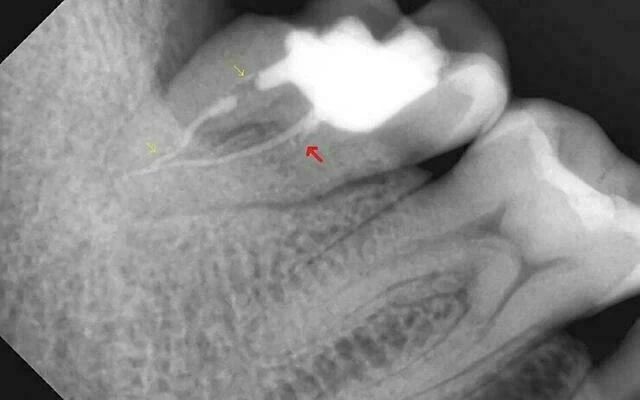

2. Thực hiện chụp phim cận chóp trước điều trị. Trên phim thấy hình ảnh trám bít ống tủy chưa kín khít (mũi tên vàng) và thiếu ống tủy phía gần (mũi tên đỏ).

Hướng điều trị: Điều trị tủy lại và làm chụp răng 47.